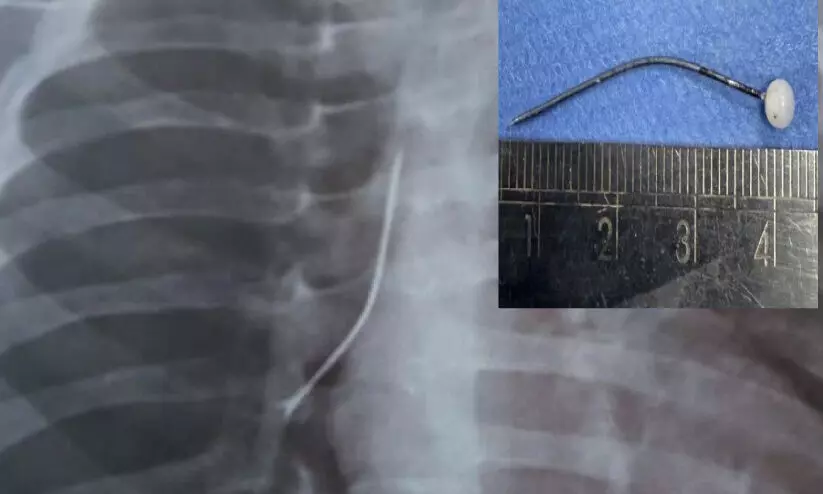

text_fieldsപിഞ്ചുകുഞ്ഞിന്റെ ശ്വാസനാളത്തിൽ സേഫ്റ്റി പിൻ കുരുങ്ങിയ നിലയിൽ (എക്സ്റേ ചിത്രം), ഇൻസൈറ്റിൽ ശ്വാസനാളത്തിൽനിന്ന്

പുറത്തെടുത്ത

സേഫ്റ്റി പിൻ

കൊച്ചി: 12 മാസം പ്രായമുള്ള കുഞ്ഞിന്റെ ശ്വാസനാളത്തിൽനിന്ന് നാല് സെന്റീമീറ്റർ നീളമുള്ള സേഫ്റ്റി പിൻ വി.പി.എസ് ലേക്ഷോർ ആശുപത്രിയിൽ വിജയകരമായി നീക്കംചെയ്തു. ശ്വാസമെടുക്കാൻ കടുത്ത ബുദ്ധിമുട്ട് അനുഭവപ്പെട്ടതിനെ തുടർന്നാണ് കുട്ടിയെ ആശുപത്രിയിലെ അത്യാഹിത വിഭാഗത്തിൽ എത്തിച്ചത്. സേഫ്റ്റി പിൻ കുട്ടിയുടെ ശ്വാസനാളത്തിൽ കുടുങ്ങിയതായി എക്സ്റേയിൽ സ്ഥിരീകരിക്കുകയായിരുന്നു.

തുടർന്ന് അടിയന്തരമായി ബ്രോങ്കോസ്കോപ്പി നടത്തി. ആശുപത്രിയിലെ പൾമണറി ക്രിട്ടിക്കൽ കെയർ ആൻഡ് സ്ലീപ് മെഡിസിൻ വകുപ്പിലെ കൺസൽട്ടന്റായ ഡോ. മുജീബ് റഹ്മാന്റെ നേതൃത്വത്തിലാണ് ബ്രോങ്കോസ്കോപ്പി നടത്തിയത്. ശ്വാസനാളത്തിൽ പിൻ ഉണ്ടെന്ന് ഇമേജിങ്ങിലൂടെയാണ് സ്ഥിരീകരിച്ചതെന്നും കുട്ടി ഇപ്പോൾ സുഖംപ്രാപിച്ചു വരുന്നതായും ഡോ. മുജീബ് റഹ്മാൻ പറഞ്ഞു.